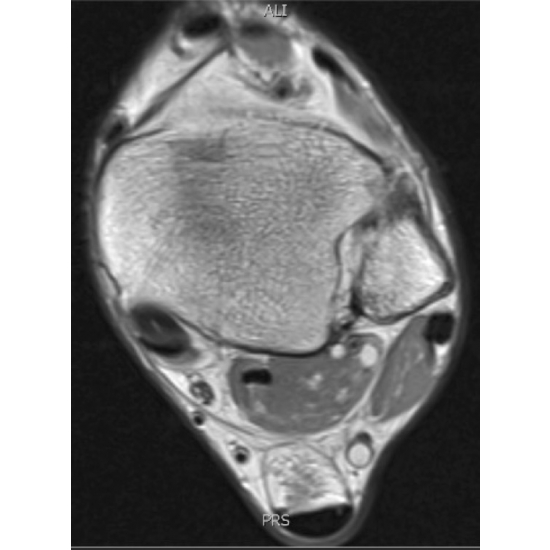

| Differentiating Between Victims And Culprits: A Case Of Left Ankle Pain - Page #3 | |||